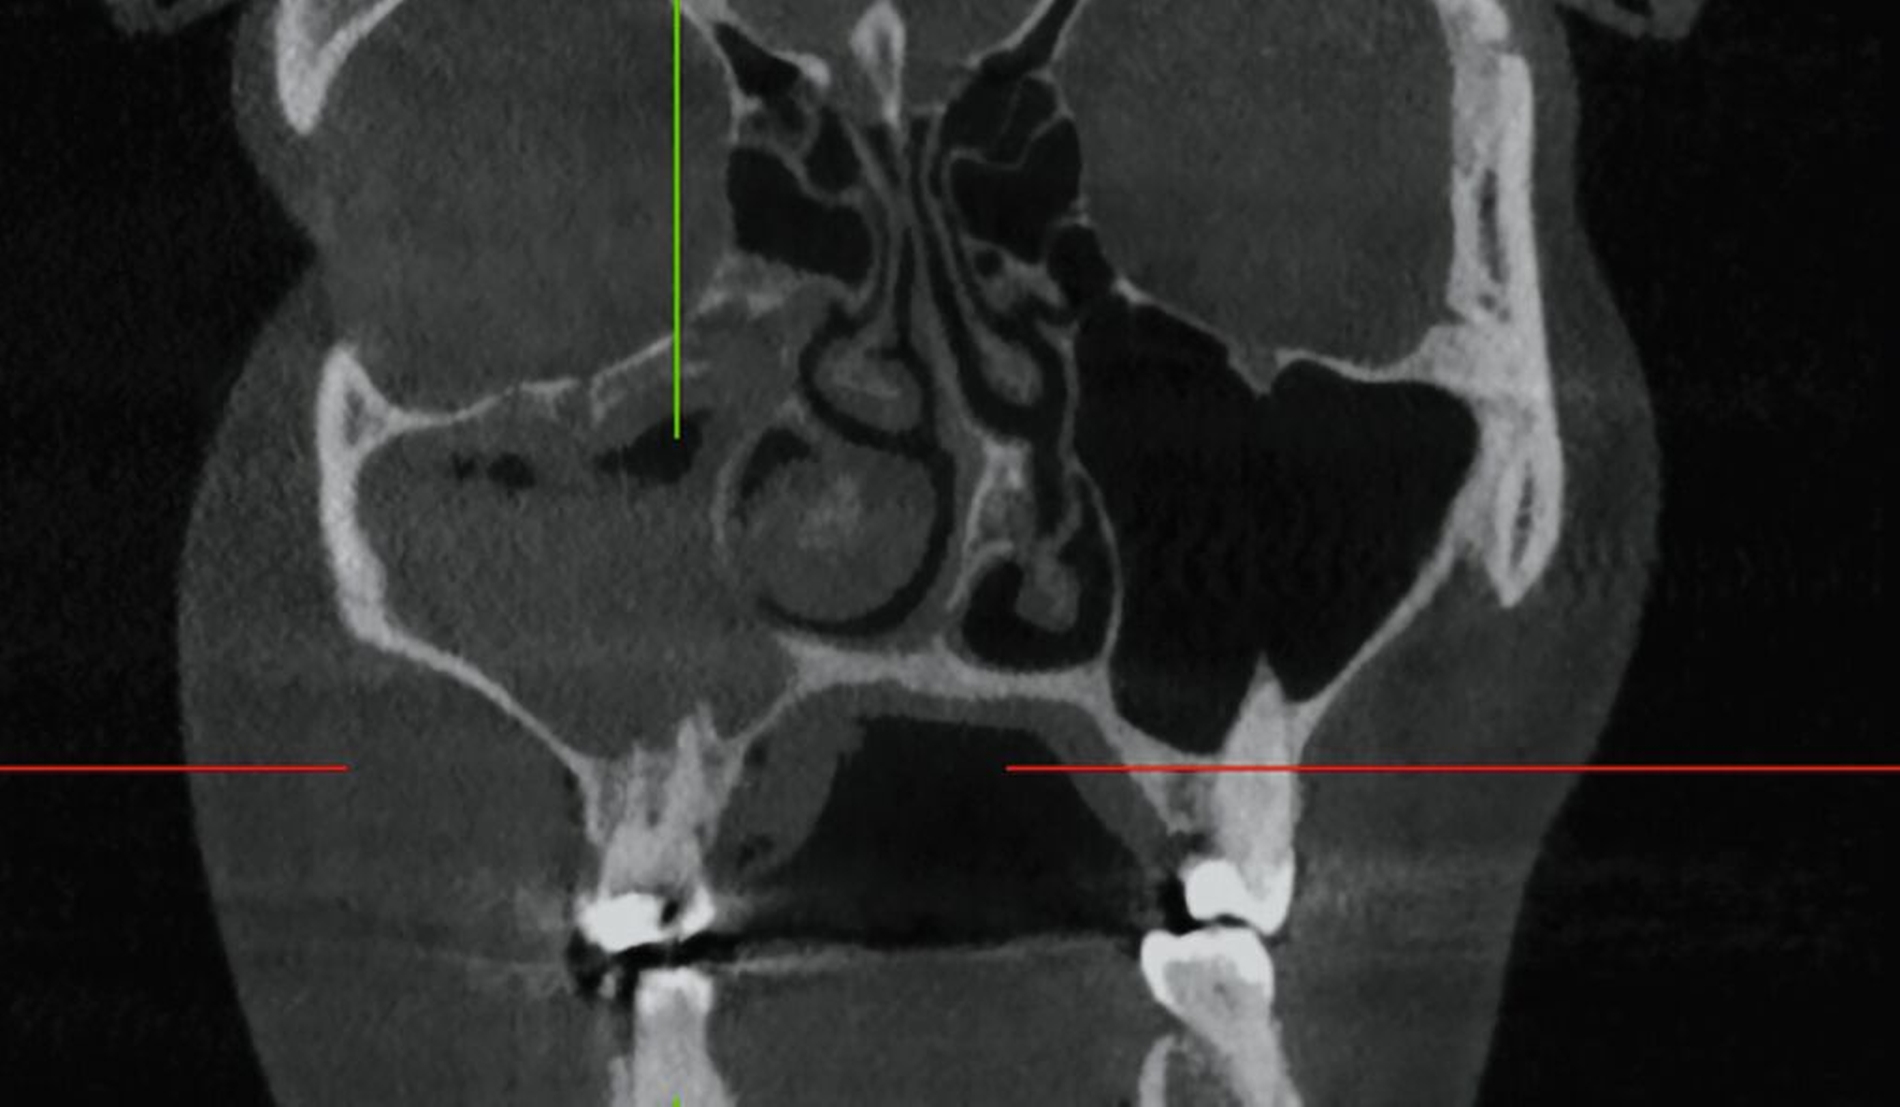

Das DVT zeigte eine Spiegelbildung im rechten Sinus maxillaris, jedoch keinen stark auffälligen knöchernen Befund (Abbildung 2). Die Patientin wurde zu intravenöser Antibiose, Analgesie und Ernährung über eine nasogastrale Sonde stationär aufgenommen. Im Verlauf wurde eine Verbandsplatte per Intraoralscan angefertigt und eine Operation zur Nekrosektomie und Wundanfrischung geplant. Zum Zeitpunkt des operativen Eingriffs hatten sich bereits Teile der vestibulären und der palatinalen Schleimhaut abgelöst. Nach Debridement zeigte sich ein großflächiges Areal mit freiliegendem Knochen. Der Zahn 15 wurde bei Lockerungsgrad III entfernt (Abbildung 3).